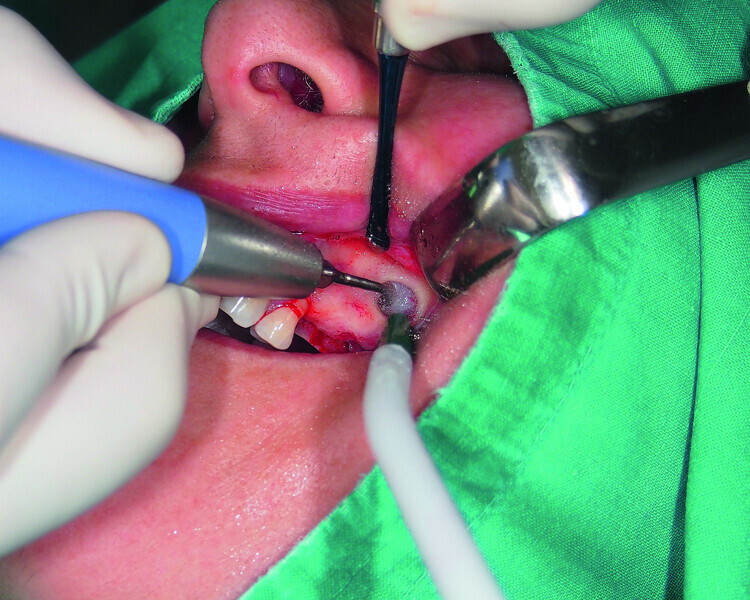

Fig. 16: Mandibular ridge splitting with vertical cuts.

Fig. 17: Creation of space in between the buccal and lingual lamina with the intact attached periosteum on the buccal.